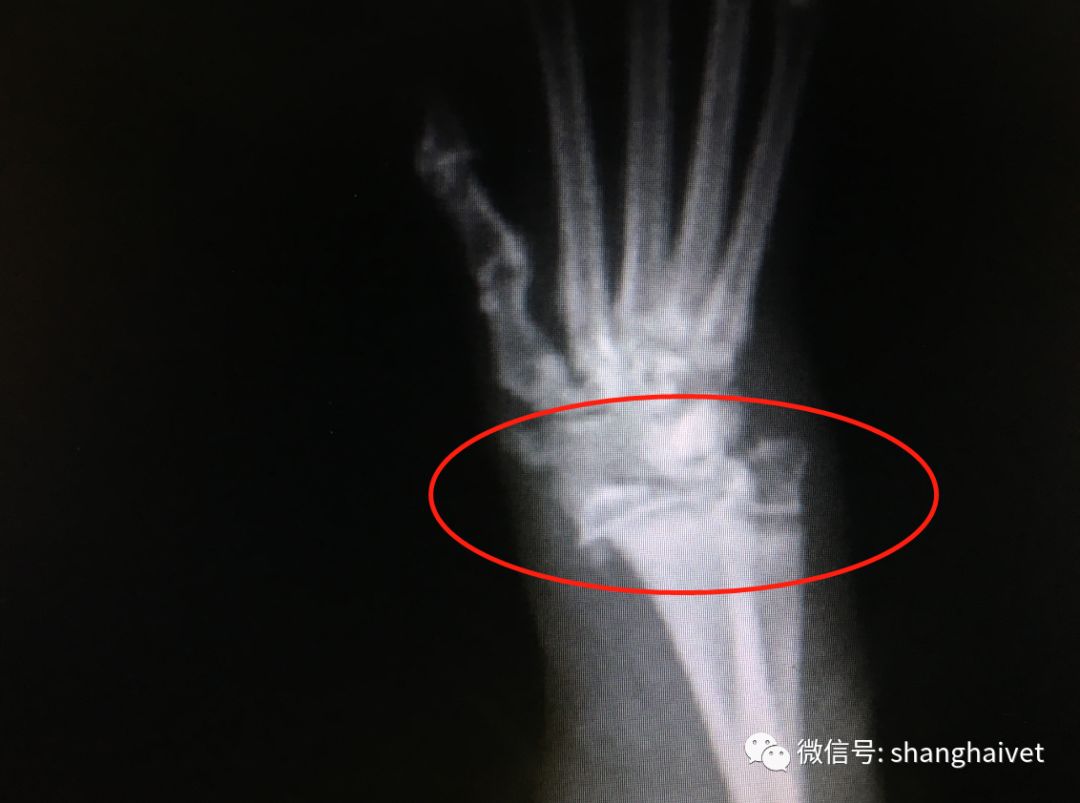

X光检查发现左侧桡尺骨中段骨折,左侧掌骨骨折,右前肢腕关节错位。

▲X光显示左侧桡尺骨中段骨折、右侧腕关节错位